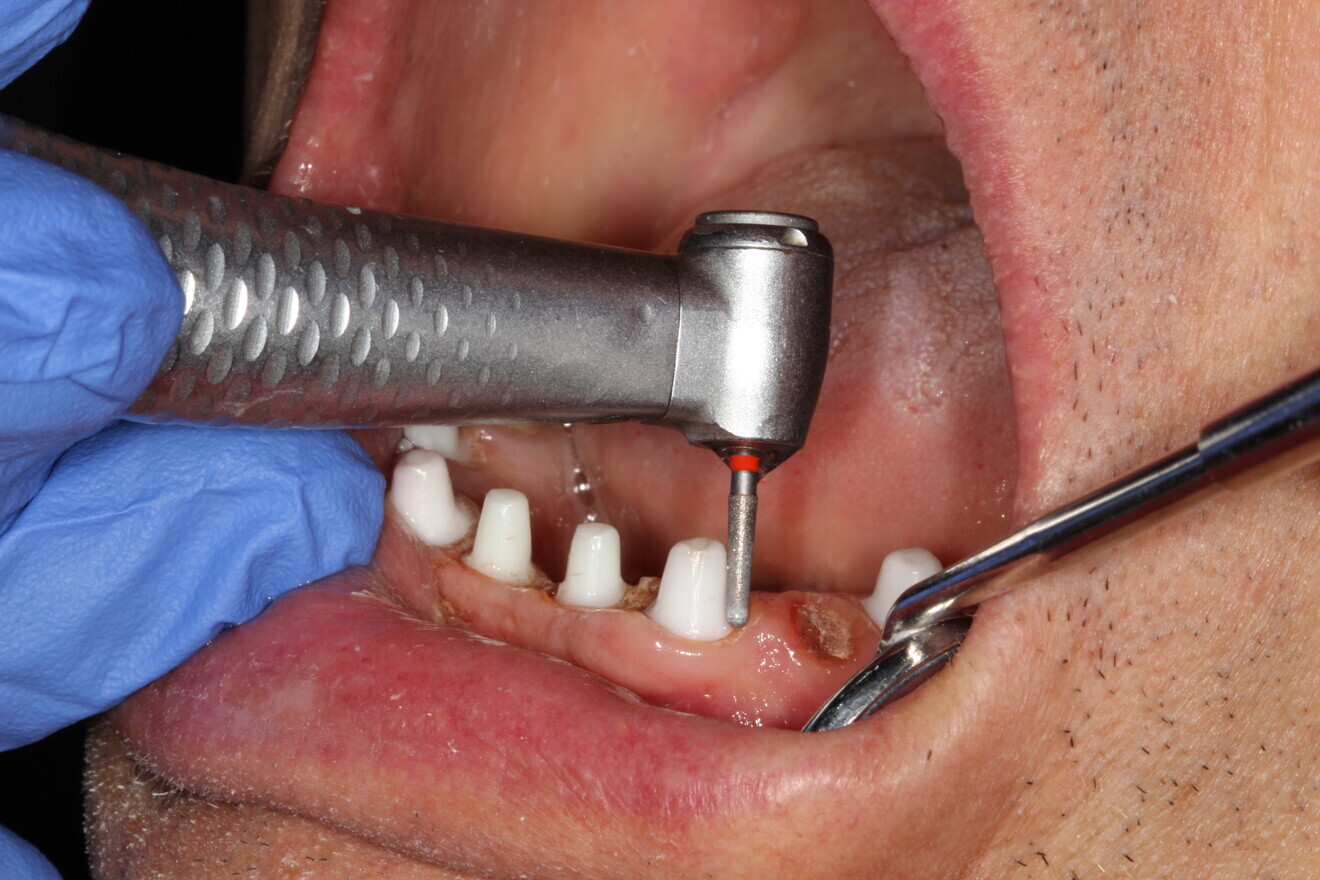

Fig. 10: Preparation of the abutment.

At five months of healing, the remaining failed dentition was removed and the soft tissue allowed to heal for seven weeks. Preparation of the implants for the final restoration consisted of removal of the temporary restoration, preparation of the abutments using a fine (red-striped) diamond bur and fabrication of a bite jig to capture the vertical dimension of occlusion (Figs. 10 & 11). This would be used when preparing the implants to verify proper reduction of the abutments. All the implants were prepared to allow passive draw, and haemostatic agent and retraction paste were placed at the sulcus (Fig. 12).